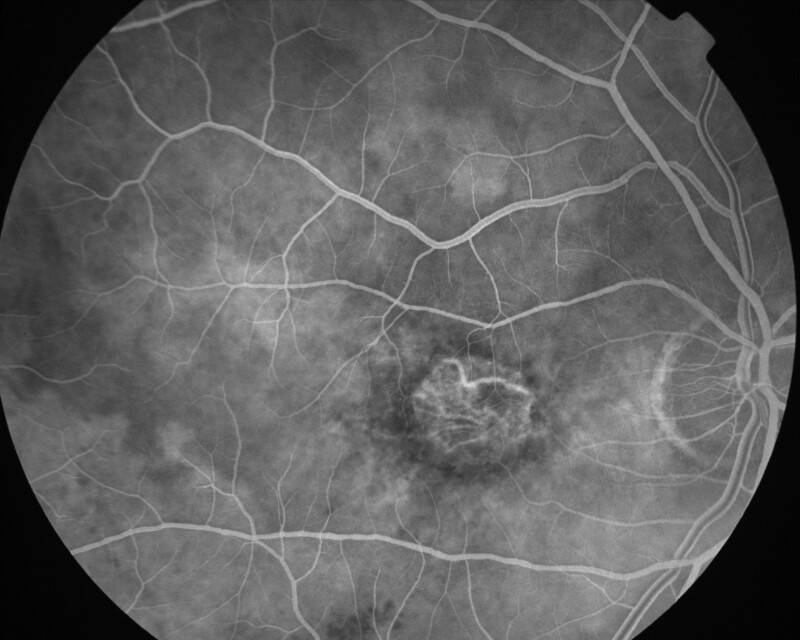

ATROPHIE AREOLAIRE CENTRALE